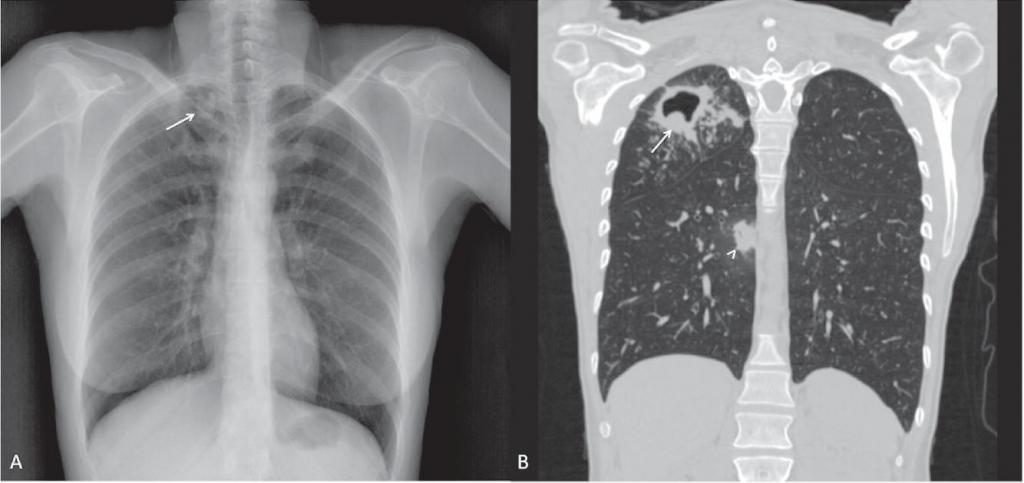

На рентгенограмме обнаруживается при туберкулезе:

- Диссеминированном. Множество мелких, хорошо очерченных, или более крупных пятен, есть каверны.

- Очаговом. Уплотнение находится не ниже 2 ребра, вокруг могут быть фиброзные тяжи, усилен легочный рисунок.

- Инфильтративном. Уплотнения правильной округлой формы на рентгеновском снимке в верхней легочной доле.

- Казеозной пневмонии. Множество полостей распада с неровными краями, очагами отсева, смещением средостения в больную сторону груди.

Инфильтраты при туберкулезе зависят от формы данного заболевания:

- Диссеминированный туберкулез сопровождается множественными мелкими очагами до 2 мм в диаметре,

- Очаговый , имеет один или несколько теней округлой, эллиптической, реже вытянутой формы с низкой интенсивностью, при которой очаги поражений темнее костной ткани,

- Казеозная форма является самой тяжелой и сопровождается затемнением нескольких долей или даже целого легкого, тень изменяется по мере распада от менее интенсивной до более выраженной,

- Кавернозный , характеризуется очаговым затемнением с просветом посередине (каверна).

Это наиболее распространенная форма туберкулеза, которая встречается более чем в 60 % случаев. Она характеризуется распространенным некрозом (гибелью) ткани легкого. В зависимости от того, что показывает флюорография легких, выделяют несколько подтипов инфильтративного туберкулеза:

- круглый инфильтрат — затемнение овальной или округлой формы в верхних отделах легких, чаще всего под ключицей;

- облаковидный инфильтрат — тень однородной структуры с неровными границами;

- краевой инфильтрат — тень имеет форму треугольника, вершина которого направлена к корню легкого;

- дольковый инфильтрат — представляет собой группу слившихся очагов различной плотности;

- лобит — тень больших размеров, охватывающая целую долю легкого, имеет неоднородную структуру.